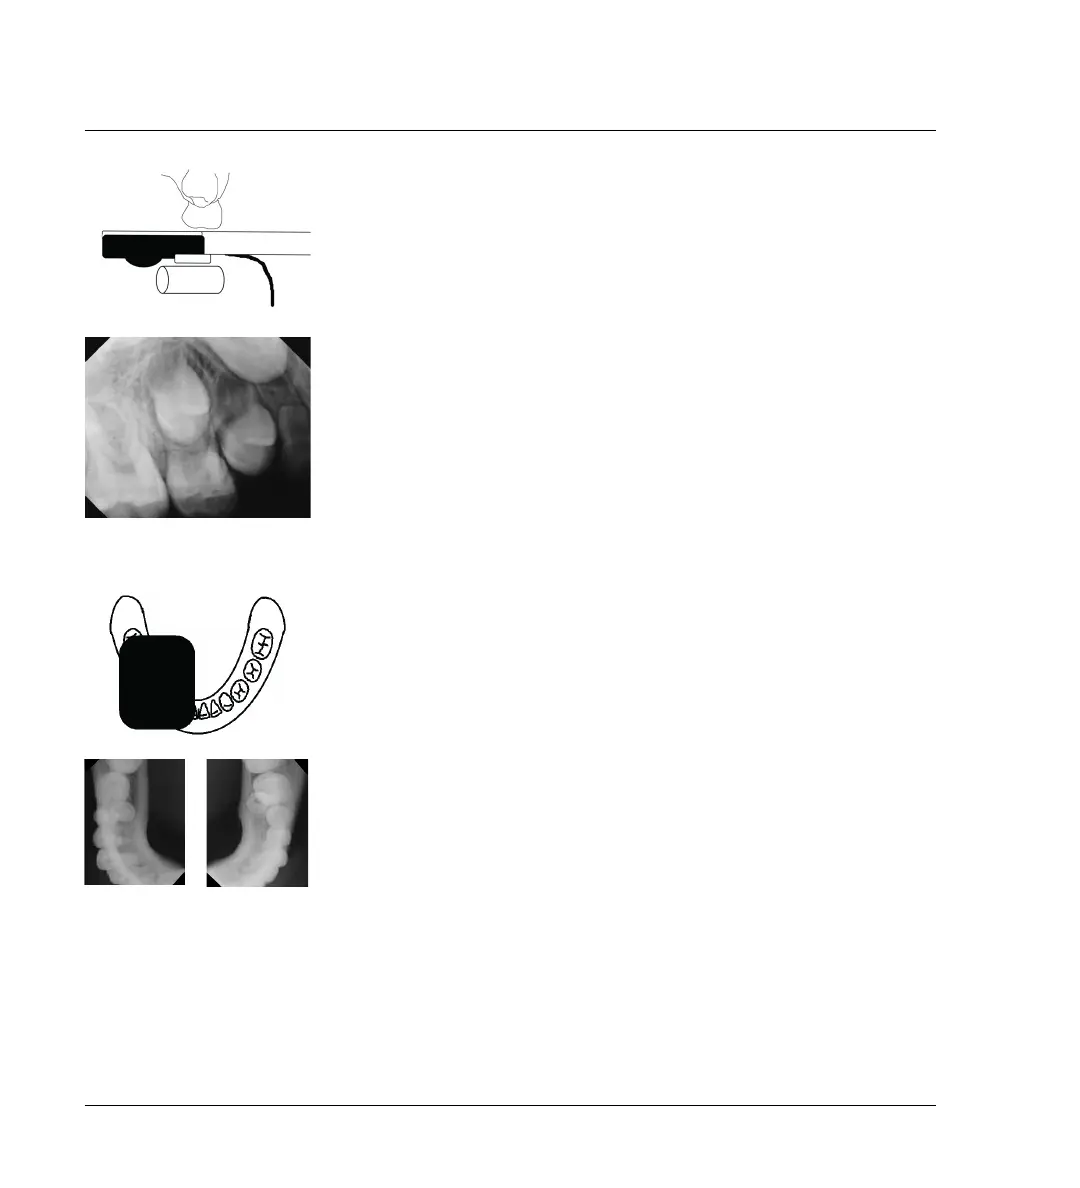

Modified Occlusal Technique

Place the sensor parallel to the occlusal plane and add a cotton roll for pro-

tection, comfort, and support. Ask the child to close gently. Use the stan-

dard bisection angle technique to capture the image.

Two-exposure Images

In some cases, you may need to place the sensor width wise, from anterior

to posterior, on half of the arch, and then repeat for the other half.

In both cases, the sensor is placed parallel to the occlusal plane and a cot-

ton roll is added for protection, comfort, and support. Ask the child to close

gently. Use the standard occlusal technique to capture the image.